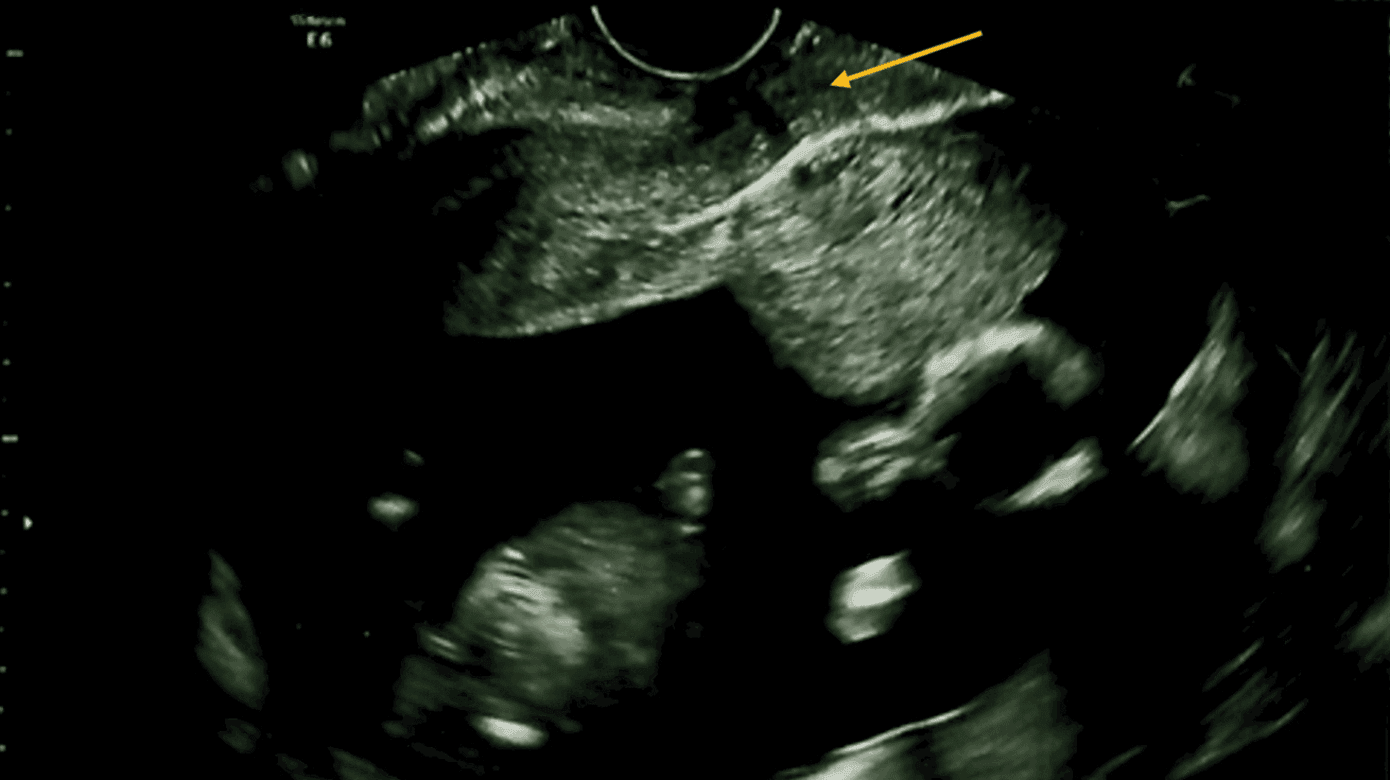

På hospitalet blev der anlagt et permanent kateter à demeure (KAD), og blæren blev tømt for 950 ml klar urin. Ved abdominal palpation var uterus mindre end forventet. Ved transvaginal UL-skannning fandt man en intrauterin graviditet svarende til GA. Fundus uteri var beliggende i fossa Douglasi og med cervix aflang og udtyndet (Figur 1A). Ved den gynækologiske undersøgelse fandtes uterus øm og posteriort placeret. Patienten blev diagnosticeret med inkarcereret uterus, og man forsøgte uden held at manipulere uterus ud af bækkenet. Pga. GA og stor urinretention blev KAD bibeholdt i 48 t., og i et forsøg på at ryste uterus ud af bækkenet blev patienten anbefalet at udføre yogastillingen downward facing dog. Her står man på alle fire med strakte ekstremiteter og med sædet i vejret. Patienten udførte yogaøvelsen a fem minutters varighed. Ved kontrol to dage senere seponeredes KAD, og patienten havde ikke længere urinretention. Ved abdominal palpation var uterus svarende til GA. Ved transvaginal UL-skanning fandt man uterus mere anteflekteret med et levende foster (Figur 1B). Patienten blev anbefalet vandladning hver tredje time. Til gennemskanningen så man en fortsat normal udviklet graviditet.